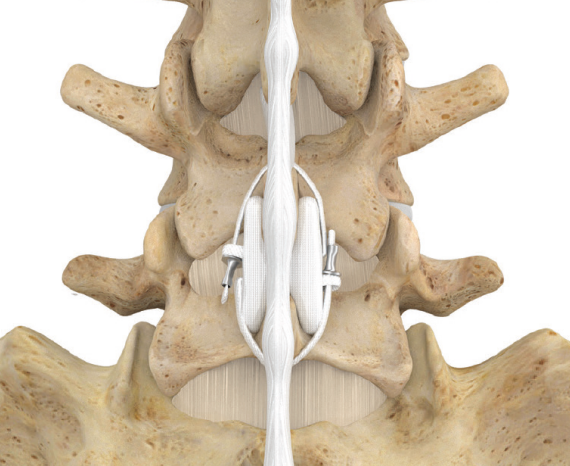

DIAM™ INTERVERTEBRAL PROSTHESIS

Dispositif d’assistance au mouvement intervertébral pour le traitement des douleurs lombaires modérées secondaires à une discopathie dégénérative.

Dispositif de stabilisation dynamique

DIAM™ INTERVERTEBRAL PROSTHESIS permet une stabilisation efficace des segments opérés tout en garantissant une certaine flexibilité. L’objectif de cette stabilisation est de réduire les lumbagos du patient tout en évitant l’arthrodèse. DIAM™ INTERVERTEBRAL PROSTHESIS est conçue pour une implantation à long terme.

- Un implant en silicone recouvert d’une enveloppe en polyester tissé, conçu pour être inséré entre deux apophyses épineuses adjacentes de la colonne lombaire.

- Des bandes en polyester, fixées par des bagues de sertissage en titane, maintiennent le dispositif solidement en place.